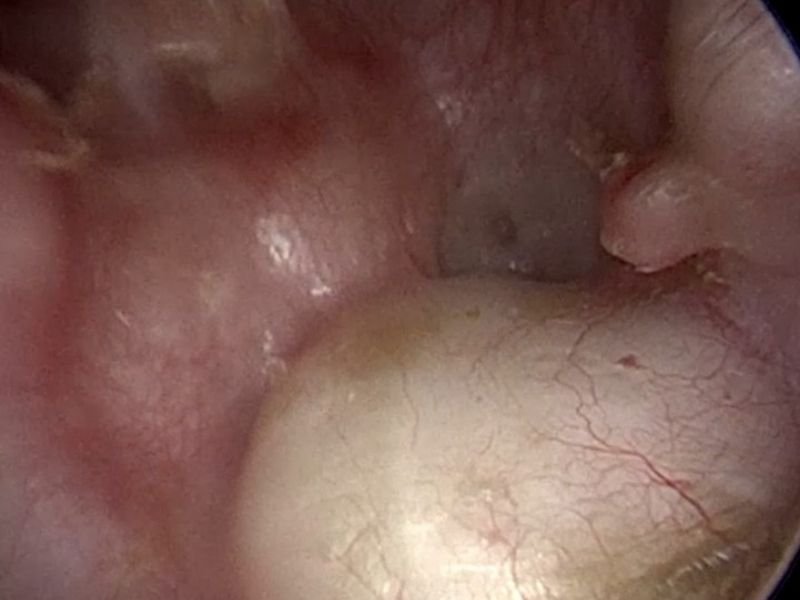

O implante coclear é um dispositivo eletrônico que substitui a função da cóclea danificada ou ausente. Ele consiste em duas partes principais: uma unidade externa, que capta e processa os sons, e uma parte interna, implantada cirurgicamente, que estimula diretamente o nervo auditivo. Ao contrário de aparelhos auditivos, que amplificam sons, o implante coclear converte os sinais sonoros em impulsos elétricos que o cérebro interpreta como som.